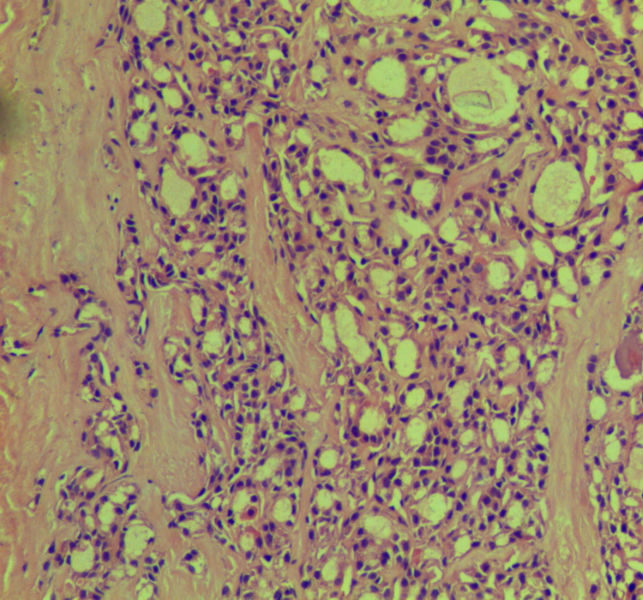

女,45岁,体检发现颈前区一结节,术中送检甲状腺左腺叶,发现一界清结小1*0.8cm,灰黄色。术中诊断滤泡性肿瘤伴包膜累及,局部疑包膜穿破,滤泡癌可能,待石蜡报告。石蜡连续切片形态见图,可见明显包膜穿破,诊断为滤泡性癌。患者借片到上级医院会诊,结果为:包膜内滤泡癌伴包膜累及。请问有包膜内滤泡癌的提法吗?这个病例怎么诊断啊?请各位老师多指导。

• 这个是滤泡性癌吗图4

图4

明确的甲状腺滤泡癌。没有什么包膜内滤泡癌的说法。

滤泡癌,他们可能指包膜浸润,但未到包膜外的意思